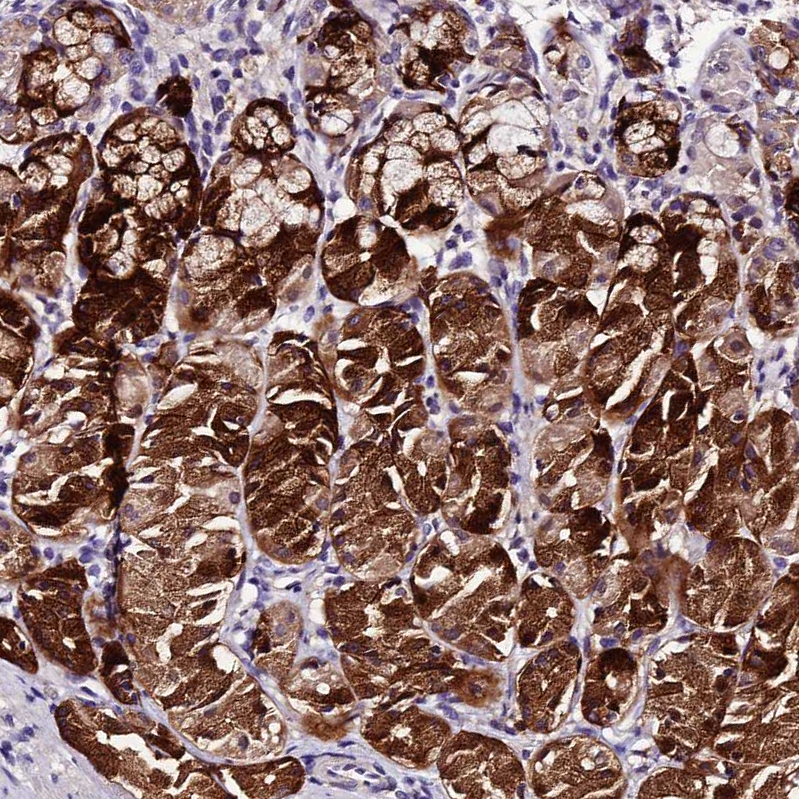

Immunohistochemical staining of human stomach shows strong cytoplasmic positivity in glandular cells.